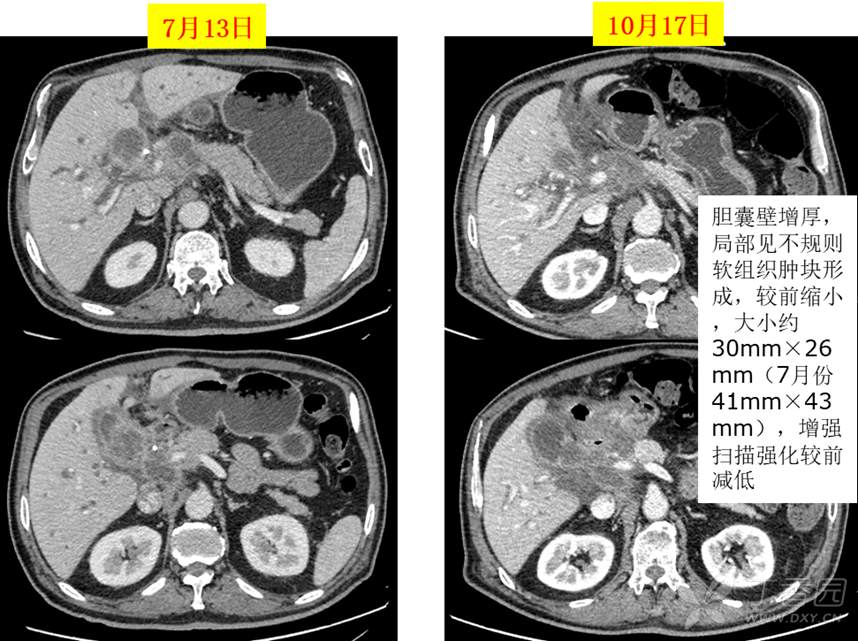

复查影像前后对比为PR,如下图: